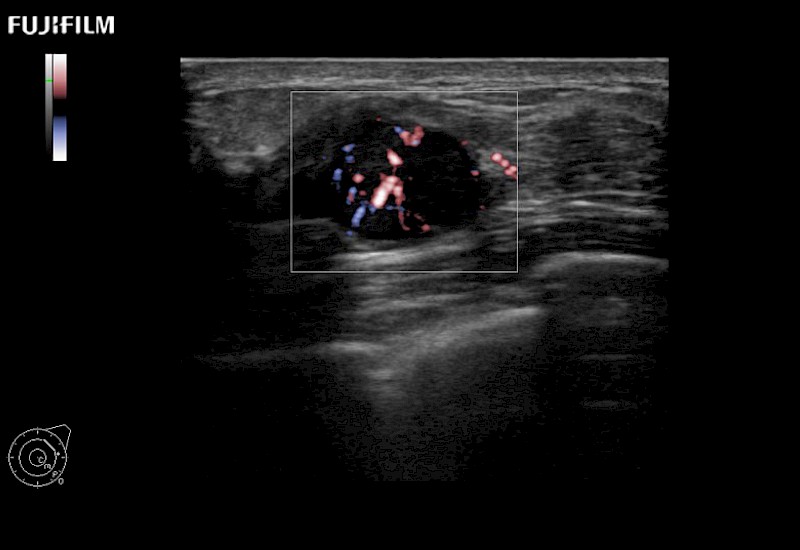

Extraordinary high-resolution digital imaging

Multi-Parametric imaging modalities